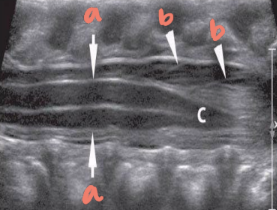

solid white arrow

echogenic epidural fat

vb

vertebral bodies

d

intervertebral disks

p

spinous processes

arrowheads

arachnoid/dural layer

e

epidural space

*

subarachnoid space w/ CSF

sc

hypoechoic spinal cord